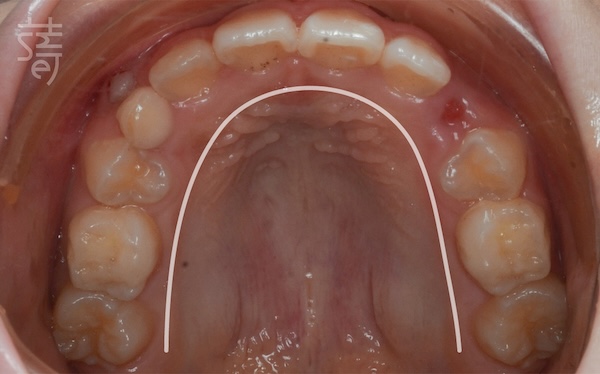

兩年後回診,X 光片上清楚顯示小緹的牙列變整齊了、牙弓更開展,嘴型也能自然閉合。那些早期努力的累積,就這樣安靜卻確實地發生在孩子身上。

Two years later, Ti returned for a follow-up, and the X-rays told the story clearly: a broader arch, straighter teeth, and a relaxed, natural lip seal. The quiet, steady work of early treatment had taken root.

媽媽笑著分享:「兩年間小緹改變很多,慢慢長出自信,各種場合總能自在露齒笑!」她很慶幸自己在孩子的早期階段,做了這個正確的決定。

Her mother put it simply—Ti was still shy, but she carried herself with more ease, smiling freely in a way that felt new and self-assured.